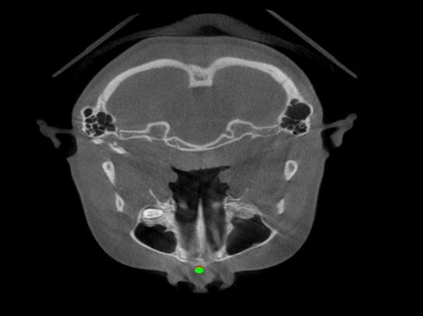

Detecting 3D landmarks on cone-beam computed tomography (CBCT) is crucial to assessing and quantifying the anatomical abnormalities in 3D cephalometric analysis. However, the current methods are time-consuming and suffer from large biases in landmark localization, leading to unreliable diagnosis results. In this work, we propose a novel Structure-Aware Long Short-Term Memory framework (SA-LSTM) for efficient and accurate 3D landmark detection. To reduce the computational burden, SA-LSTM is designed in two stages. It first locates the coarse landmarks via heatmap regression on a down-sampled CBCT volume and then progressively refines landmarks by attentive offset regression using multi-resolution cropped patches. To boost accuracy, SA-LSTM captures global-local dependence among the cropping patches via self-attention. Specifically, a novel graph attention module implicitly encodes the landmark's global structure to rationalize the predicted position. Moreover, a novel attention-gated module recursively filters irrelevant local features and maintains high-confident local predictions for aggregating the final result. Experiments conducted on an in-house dataset and a public dataset show that our method outperforms state-of-the-art methods, achieving 1.64 mm and 2.37 mm average errors, respectively. Furthermore, our method is very efficient, taking only 0.5 seconds for inferring the whole CBCT volume of resolution 768$\times$768$\times$576.